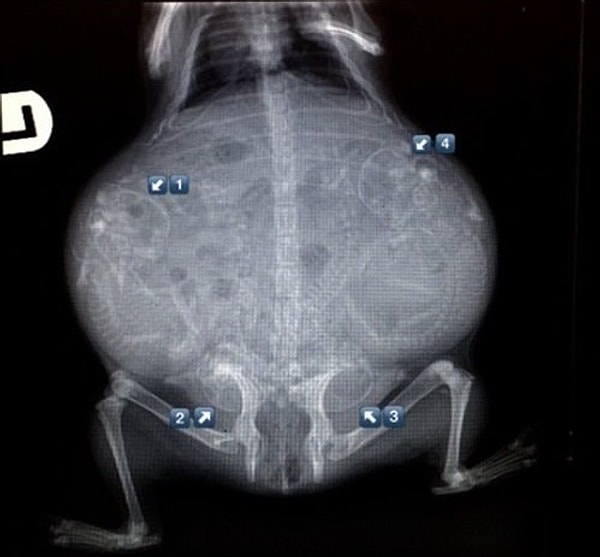

9. Морская свинка

14. Снова морская свинка